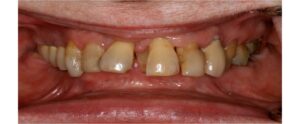

Η Προσθετικη οδοντιατρικη ειναι ο κλαδος της οδοντιατρικης που ασχολειται με την αποκατασταση μεγαλης η μικρης νωδοτητας στον οδοντικο φραγμο.

Η Προσθετικη Οδοντιατρικη χωριζεται σε

- Ακινητη προσθετικη, δηλαδη στεφανες και γεφυρες

- Κινητη προσθετικη, δηλαδη μερικες και ολικες οδοντοστοιχιες

- Προσθετικη επι εμφυτευματων